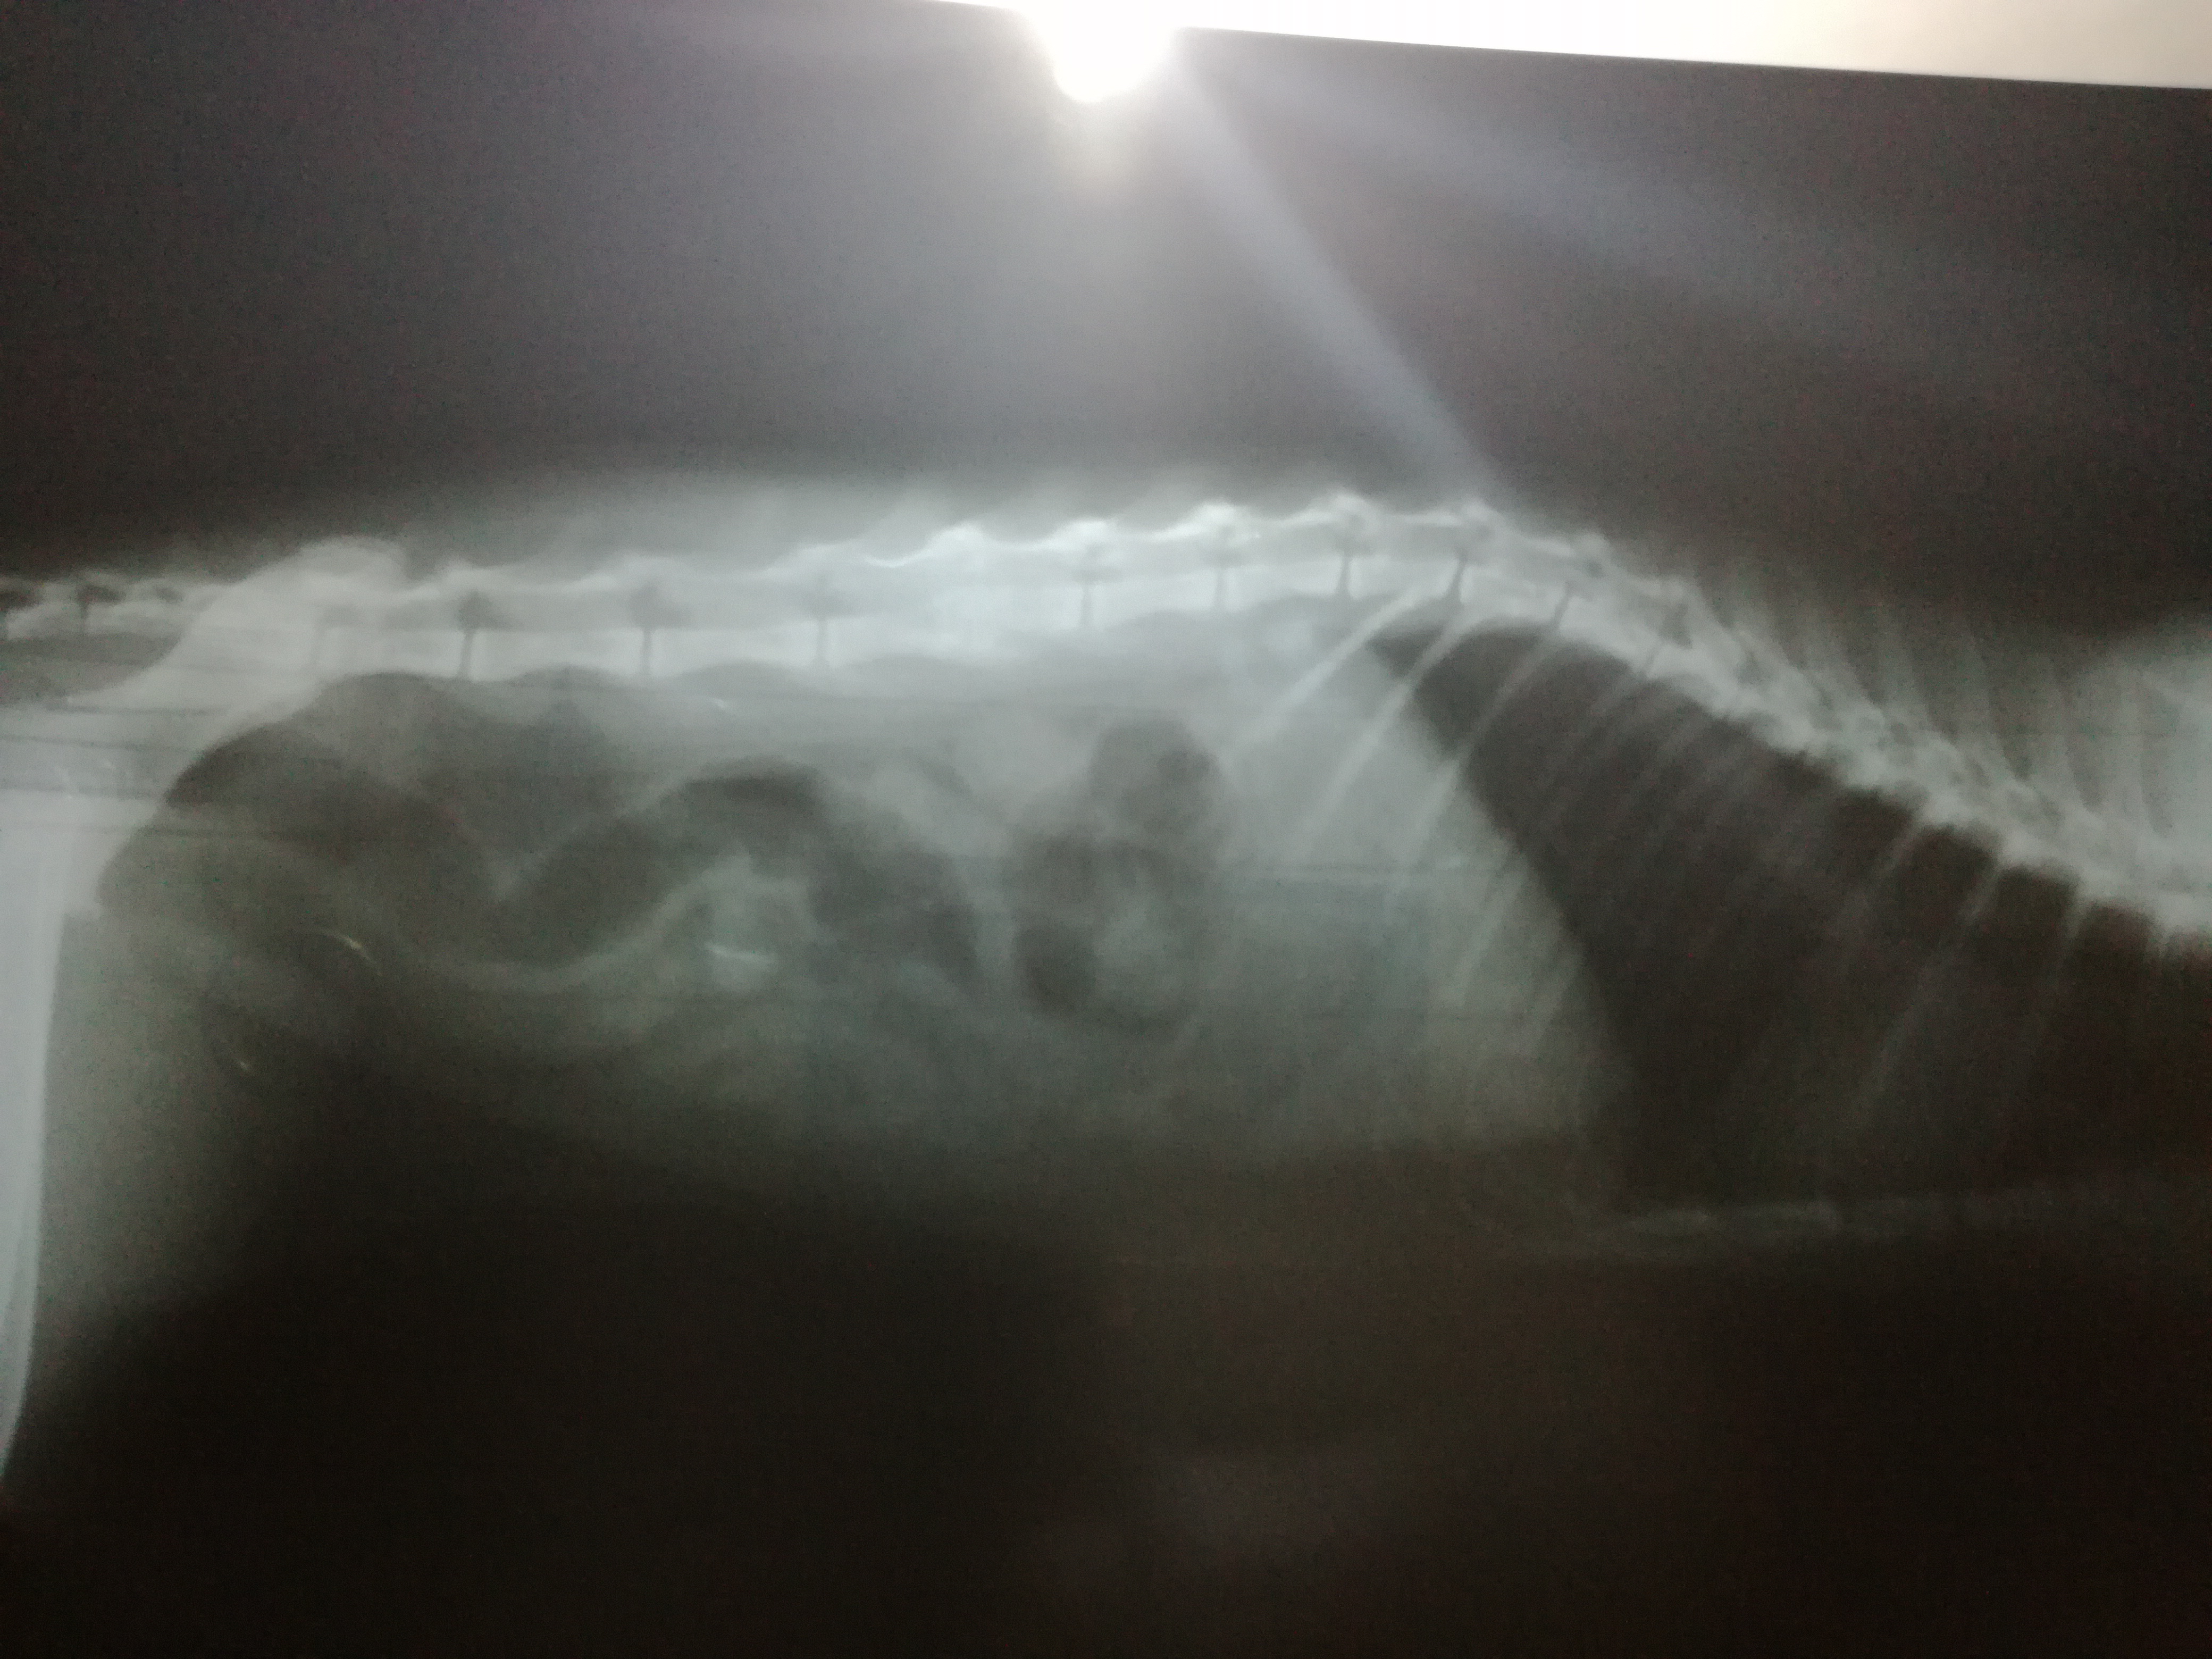

گربه ماده ده ماهه دارم. دوسه ماهش بود پیداش کردم. بعد دوسه هفته موقعی که نوازش میکردم، به کمرش که میرسیدم جیغ میکشید. ولی نه لنگ میزد نه زمینگیر بود. فقط یکهفته ای گوشه گیر بود و غذا نمیخورد و با دست غذا میدادم تا اینکه دوباره بازیگوشی و غذاخوردنش خوب و حتی عالی شد.

تااینکه دوهفته پیش یهو اعتصاب غذا کرد و دکتر ب کمپلکس و انتی بیوتیک تزریق کرد و قرص اسیدفولیک داد. بعد دوسه روز اسهال و استفراغ شد و بردمش متخصص رادیولوژی و عکس از دستگاه گوارشش گرفت و دکتر اتفاقی ستون مهره رو دید و گفت چندماه پیش مهره کمرش شکسته بود و بد جوش خورد و چون درد داشت غذا نمیخورد و بیجهت انتی بیوتیک تزریق کرد بخاطر همین اسهال استفراغ شد.

سوال من اینه که فحل شده بیقراری میکنه. میتونم جفت بزنم؟ جنین به مهره هاش فشار نمیاره و خطر نداره؟

عکس براتون میفرسم.